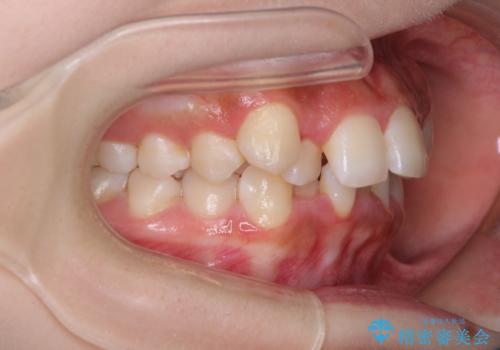

- 上顎の八重歯と、上下前歯のデコボコを気にして来院された患者様です。

奥歯の咬み合わせを見ると、上顎臼歯が下顎に対して前方にあり、叢生改善により口元が突出する顔貌ではなかったため、上顎左右第一小臼歯2本を抜歯し、ワイヤー装置にて矯正治療を行うこととしました。

前歯部のデコボコがなくなったため、歯磨きしやすくなり、非常に清潔な状態になりました。